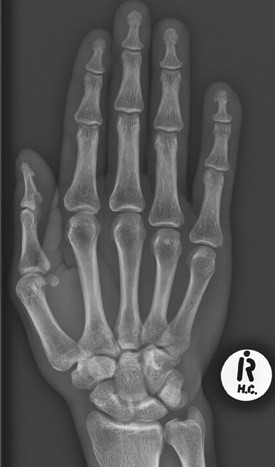

Загальна рентгенографія

Педіатрія